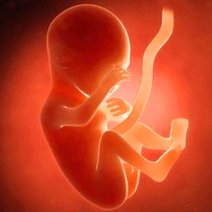

胎儿亲子鉴定有一定程序,尤其是看是不是胎儿的父亲,这个父亲他要有提起申请,要进行身份证备案、核实,然后一般在规定的医院进行胎儿亲子鉴定,是规定的医院,一般都是三甲医院。一般都是小的孕周取标本,12周左右就是取绒毛,在大孕周取羊水,当然也有从母血里面做胎儿染色体的微创检查,但是准确率不如取羊水、取绒毛的准确率高。进行胎儿亲子鉴定也可以取毛发,比如取父亲的毛发,不是取他脱落的毛发,一定是要从他头上有毛囊的毛发,要能培养出染色体的有毛囊毛发。做亲子鉴定是有专职的医院,有资质的医生进行,要求做亲子鉴定的母亲,一定要把各种材料、证明都准备好。

胎儿是可以做亲子鉴定的。通常有采集孕妇静脉血的无创亲子鉴定、绒毛亲子鉴定和羊水亲子鉴定等,可以通过鉴定其中的DNA来判断和确认亲缘关系。 无创亲子鉴定...5683人收听

胎儿能做亲子鉴定吗【胎儿可以做亲子鉴定吗】

首先明确胎儿是可以做亲子鉴定的。一般的胎儿在10周到15周之间,最好在10周到12周之间可做亲子鉴定。但是胎儿做亲子鉴定,一般都要在三甲医院以上,由妇产科主任...4889人收听